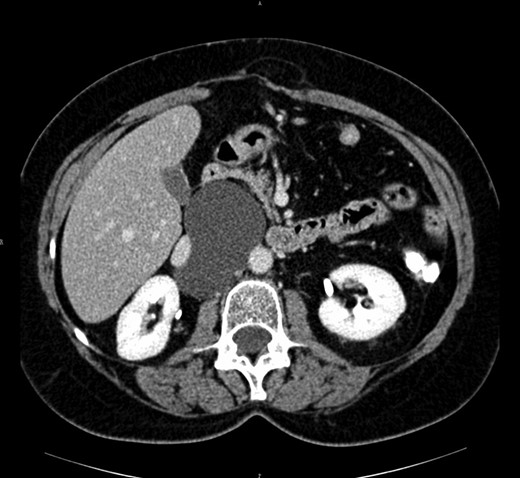

The abdominal computed tomography scan with contrast revealed a huge (10 cm of diameter) retroperitoneal cyst, oval shaped and containing dense fluid, located within the caval vein and the aorta, under the origin of the renal artery, partially dislocating the caval vein to the right (see Fig. 2).

Computed tomography view of the mesenteric cyst partially dislocating the caval vein.

In our first case, we performed the complete excision of the cyst by laparoscopy. The position of the trocars must be decided depending on the location of the tumor [3]. A second concern of the technique is the relation between the cyst and the major abdominal vessels. Our second case, with a huge retroperitoneal cyst highly interconnected with major abdominal blood vessels and a syncronous hiatal hernia, required a laparotomic approach. It is important in order to avoid any risk of chylous fistula to accurately seal and divide any vessel of the cyst. However, the chyle leakage from the cyst does not represent any particular concern, as long as the surgeon can accurately wash the surgical field and eventually insert a drain (see Fig. 3).